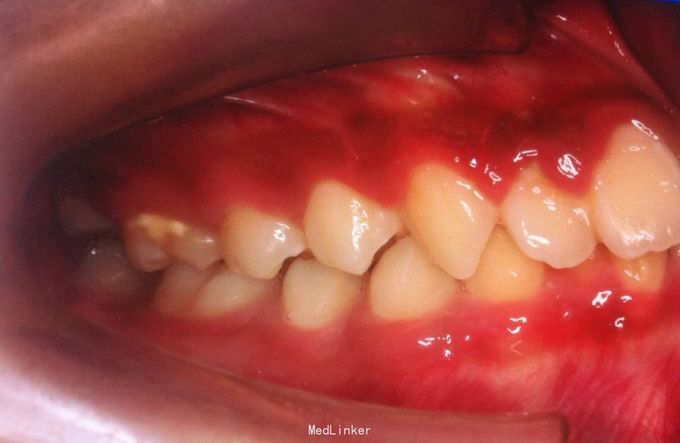

恒牙期 25正锁合 磨牙中性关系 前牙一度深覆盖深覆合 牙列拥挤 张口型异常

安氏一类 不拔牙矫治,直丝弓矫治器,排齐整平上下牙列,治疗后前牙覆合覆盖正常,磨牙中性关系,维持现有面型